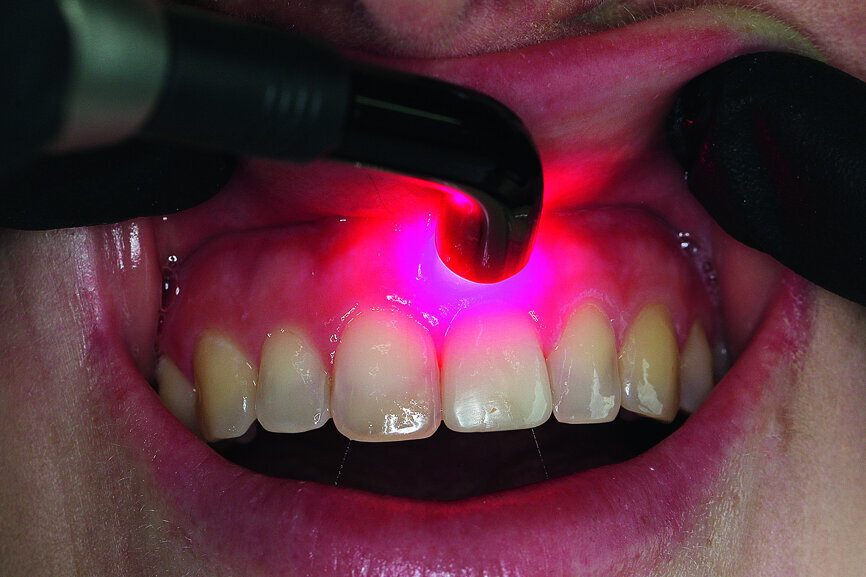

Fig. 15: Situation after one week: activation of wound healing with a soft laser of 660 nm.

The situation after the temporary restoration (Fig. 14) was aesthetic and free of inflammation. The temporary was positioned 0.5 mm short of occlusion. The patient came for a follow-up after one week. At this visit, we used the soft laser (SiroLaser Blue, wavelength of 660 nm) to activate wound healing (Fig. 15).

I also use laser in my practice depending on the indication. In the case of this patient, there was an inflammatory process at the tooth (granuloma). With the laser, I can achieve thorough disinfection of the alveolus and also activate wound healing.